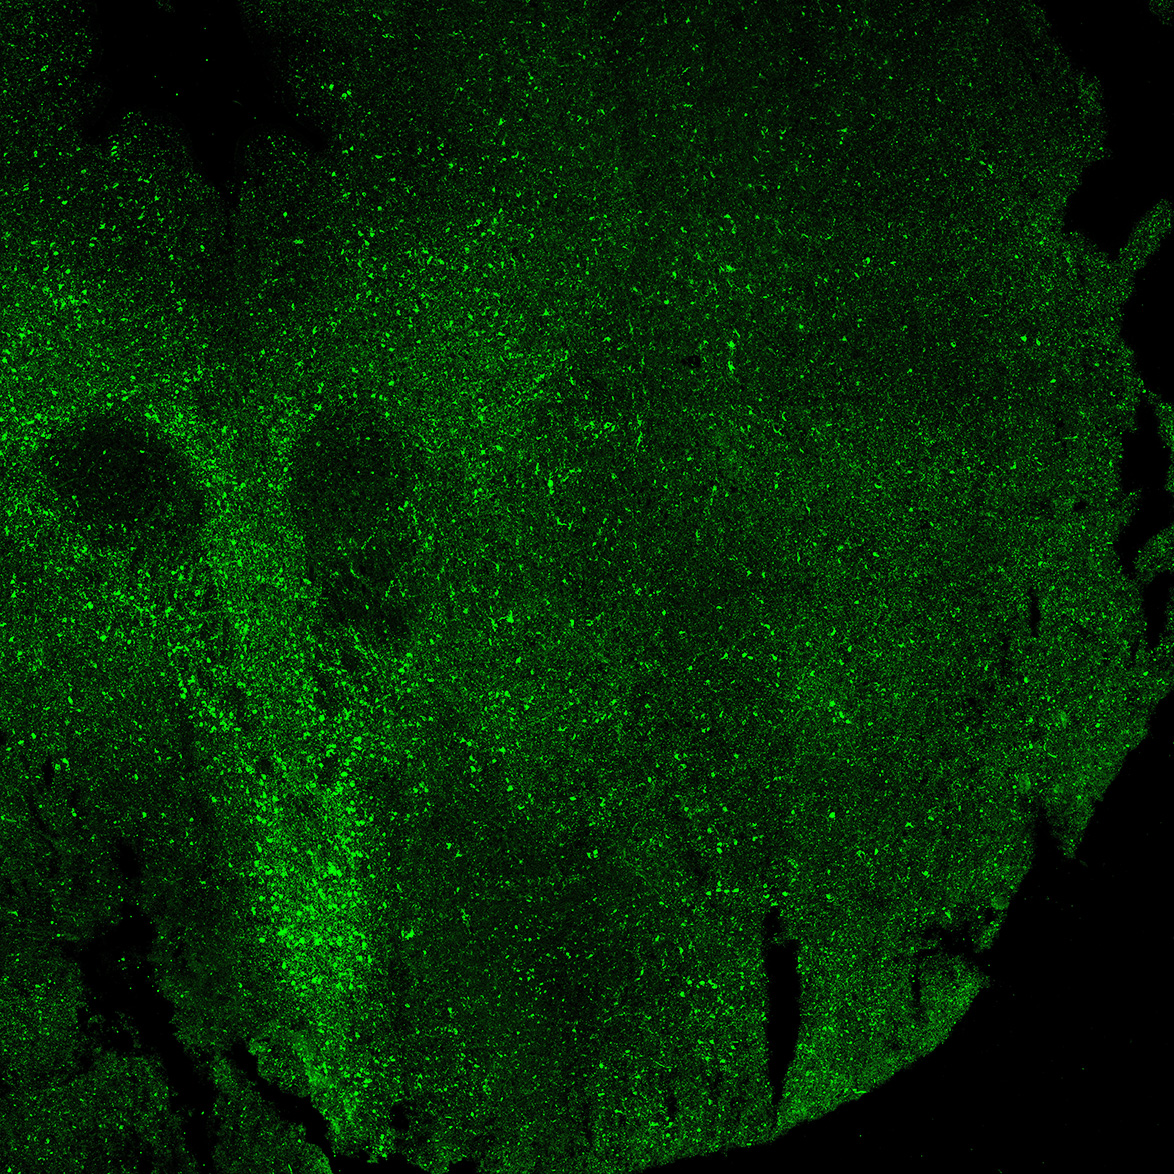

An anatomical analysis of the developing human midbrain from 6 post-conceptional weeks (PCW) to 22 PCW reveals increased tissue complexity, characterized by the emergence of dopaminergic nuclei, as highlighted by immunofluorescence analysis for tyrosine hydroxylase (TH).

MAP2

6PCW human midbrain